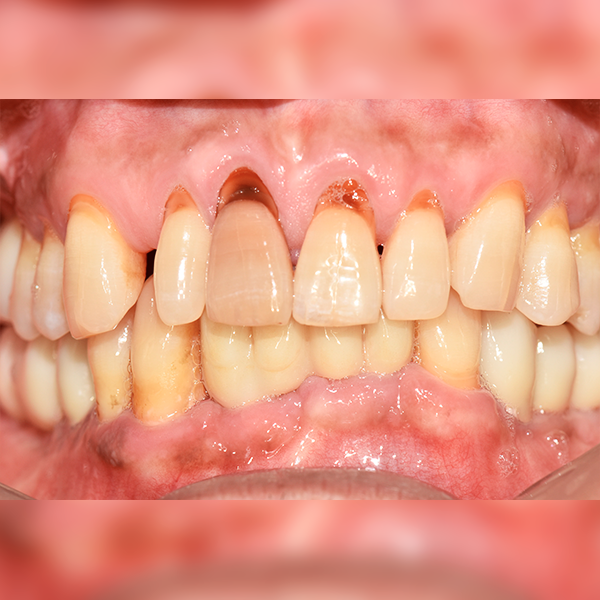

下顎/全口 / 補骨|舒眠|糖尿病

案例 102,50多歲 吳*烈 2018-08-31 / 2019-03-28